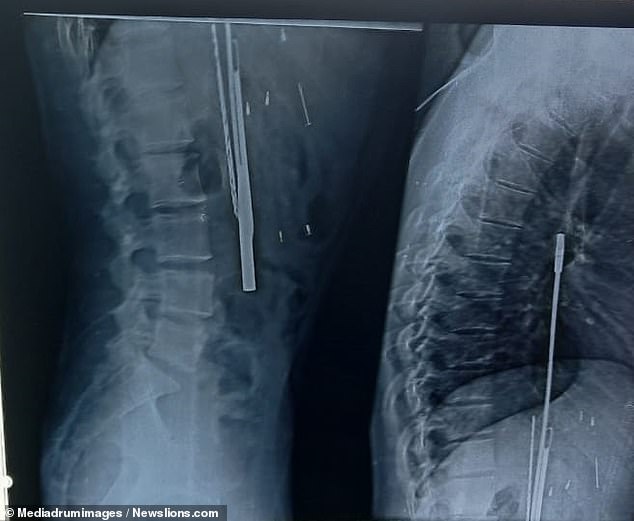

Εκεί οι γιατροί μόλις τον εξέτασαν έμειναν με το στόμα ανοιχτό. Κάτι υπήρχε μέσα στο στομάχι του και οι ακτινογραφίες το επιβεβαίωσαν. Υπήρχαν 33 αντικείμενα πολλά από αυτά αιχμηρά τα οποία είχε καταπιεί. Είχε καταπιεί ξυράφια, μαχαίρια, κατσαβίδια, πρόκες, και ότι άλλο μπορεί να φανταστεί ο ανθρώπινος νους. Οι γιατροί τον έβαλαν αμέσως στο χειρουργείο και ύστερα από μια επιτυχημένη επέμβαση του τα αφαίρεσαν.